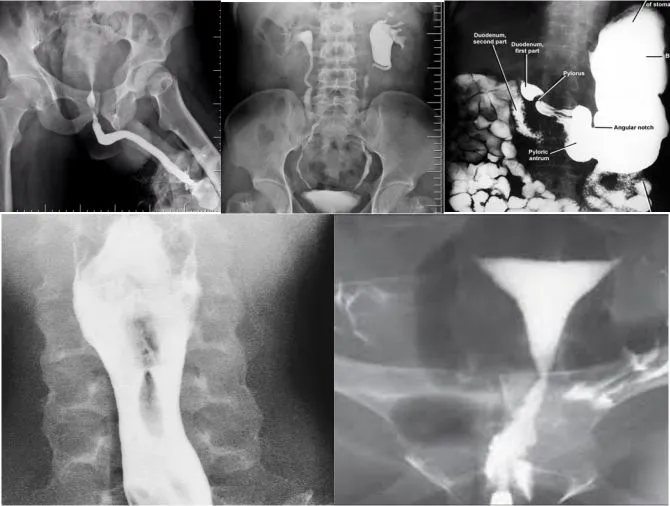

All Conventional Radiology Procedures

Barium studies, RGU, MCU, IVP, FISTULOGRAM etc...